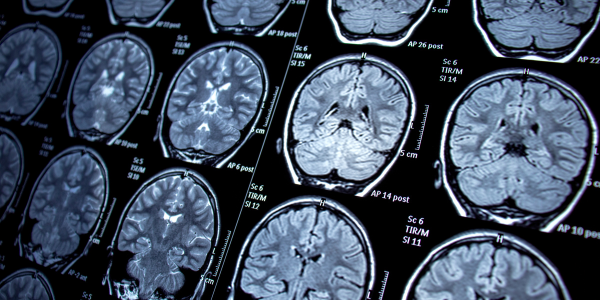

Advancing imaging

Advancing MRI technology includes more mobile and low-power MRIs may enable more frequent imaging and faster diagnosis.